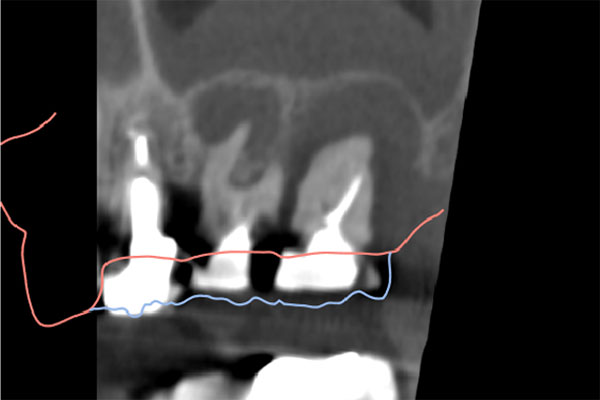

インプラント2本の予定ですので、インプラント同士をほぼ並行に埋入する計画を立てます。神経にインプラントが当たりますと、麻痺が起きたり出血の原因になりますので、

シュミレーション上でもしっかり神経とは距離をおきます。

コーンビームCT像を確認すると左側上顎の骨は無くインプラント埋入の際は上顎骨に骨造成が必要と思われたため上顎洞挙上術(サイナスリフト)を併用、インプラント埋入を行うプランとしました。

また欠損部位の大きさを考えるとサージカルガイドの使用が必要と思われたため今回使用した。さらにオペの強度を考え静脈内鎮静法下にてオペを行った。

処置前では黒い透過像(骨が無い)があるが骨造成後1年経過、インプラントテック(仮歯)を入れた際では上顎洞内及びインプラント周囲に白い不透過像(骨がある)が確認できます。